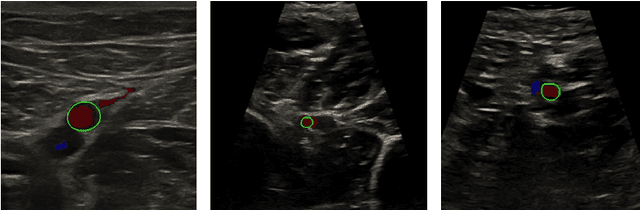

Abstract:Accurate, real-time segmentation of vessel structures in ultrasound image sequences can aid in the measurement of lumen diameters and assessment of vascular diseases. This, however, remains a challenging task, particularly for extremely small vessels that are difficult to visualize. We propose to leverage the rich spatiotemporal context available in ultrasound to improve segmentation of small-scale lower-extremity arterial vasculature. We describe efficient deep learning methods that incorporate temporal, spatial, and feature-aware contextual embeddings at multiple resolution scales while jointly utilizing information from B-mode and Color Doppler signals. Evaluating on femoral and tibial artery scans performed on healthy subjects by an expert ultrasonographer, and comparing to consensus expert ground-truth annotations of inner lumen boundaries, we demonstrate real-time segmentation using the context-aware models and show that they significantly outperform comparable baseline approaches.